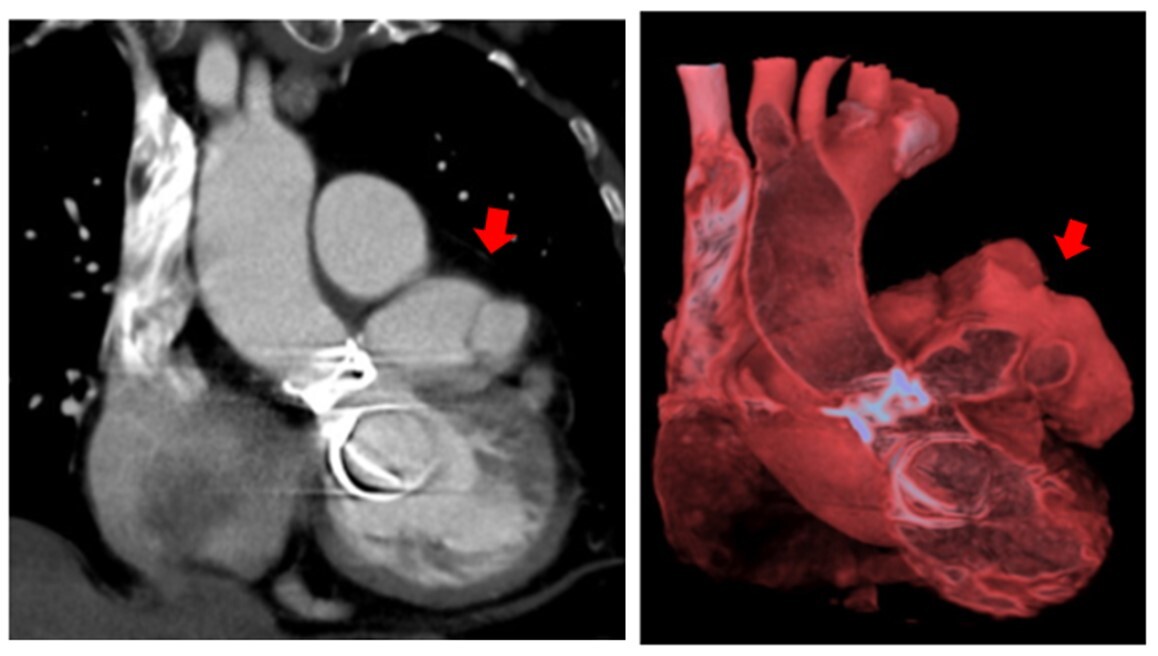

Transesophageal echocardiogram showed a large pulsatile cavity around the aortic root connected to the left ventricle at the level of the anterolateral region of the aortic prosthetic ring, consistent with a pseudoaneurysm. This finding was confirmed by a thoracic computed tomography scan, which showed a large pseudoaneurysm with polylobulated morphology and multiple sacculations that appeared to originate from the upper edge of the mitroaortic junction (Figure 4).